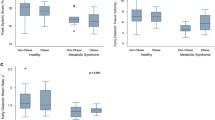

EAT area, MAT area, and VAT as well as SAT areas were significantly larger in the central obesity group than in the control group (Figure 3). The difference in IAT area (epicardial plus mediastinal adipose tissue area) between the study groups remained even after adjustment for BMI (p = 0.012), age (p < 0.001), or both (p = 0.021).

EAT area correlated inversely with LVEDV index (r = − 0.403, p = 0.037) and LV SV (r = − 0.425, p = 0.027), and there was a trend for a positive correlation between EAT area and LVMWT (r = 0.368, p = 0.054). MAT area correlated inversely with LV SV (r = − 0.427, p = 0.027) and positively with LVMWT (r = 0.399, p = 0.035). EAT area or MAT area did not correlate with LV mass, LV end-systolic volume, or ejection fraction (data not shown). There was no correlation between EAT area or MAT area and CMR findings in the control group (data not shown).